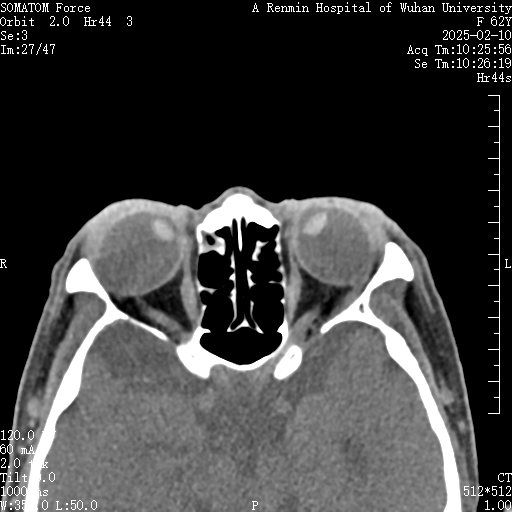

李阿姨患超高度近视已数十年。近年间,其双眼固视于内下方,右眼近乎完全内陷,虹膜及瞳孔区域几不可见,右眼视觉功能完全丧失,左眼仅残存鼻侧少许视野。严重的视觉障碍致使其生活无法自理,显著影响容貌外观,给李阿姨造成生理和心理的双重打击。她找到武汉大学人民医院眼科中心眼Ⅳ科寻求救治。

经周炼红教授细致检查,李阿姨被诊断为「高度近视性固定性内斜视」,也称为「重眼综合征」。因其近视度数超过 2000,造成眼球异常增长,眼球后极部进行性膨隆突破肌圆锥,导致眼外肌解剖关系紊乱和力学失衡。严重的后巩膜葡萄肿显著增加手术难度,术中稍有不慎就可能造成眼外肌断裂,甚至巩膜破裂或球后暴发性出血,导致失明甚至眼球萎缩等严重风险。